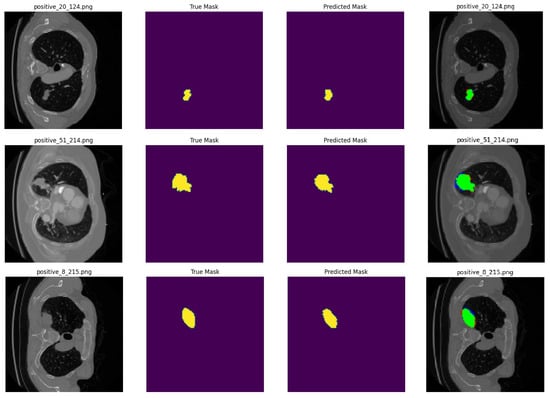

• Visualization: The input image, the actual mask, and the predicted mask from selected test samples are displayed, as given in Figure 3. These steps are repeated for each of the other segmentation models.

Figure 3. The sample prediction results are presented in the following order: first, the original image with its filename; second, the true mask of the tumor region; third, the predicted mask generated by the segmentation model; and finally, a combined image displaying all three. In the combined image, the masks are overlaid onto the original image, with green indicating correctly predicted tumor areas, blue showing missed actual tumor regions, and red highlighting healthy areas mistakenly classified as tumor.